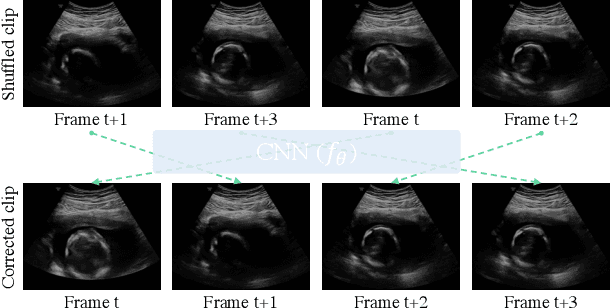

Abstract:Recent advances in deep learning have achieved promising performance for medical image analysis, while in most cases ground-truth annotations from human experts are necessary to train the deep model. In practice, such annotations are expensive to collect and can be scarce for medical imaging applications. Therefore, there is significant interest in learning representations from unlabelled raw data. In this paper, we propose a self-supervised learning approach to learn meaningful and transferable representations from medical imaging video without any type of human annotation. We assume that in order to learn such a representation, the model should identify anatomical structures from the unlabelled data. Therefore we force the model to address anatomy-aware tasks with free supervision from the data itself. Specifically, the model is designed to correct the order of a reshuffled video clip and at the same time predict the geometric transformation applied to the video clip. Experiments on fetal ultrasound video show that the proposed approach can effectively learn meaningful and strong representations, which transfer well to downstream tasks like standard plane detection and saliency prediction.